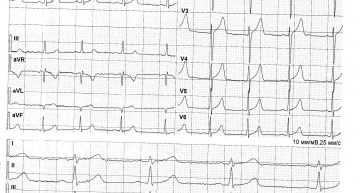

Объясните, пожалуйста, результаты всех моих исследований доступным языком. Есть ли проблемы? Что такое синдром ранней реполяризации желудочков, АВ-блокада 1 ст и АВ-блокада 2 ст Мобитц, ПМК 1 степени, дополнительная хорда ЛЖ верхушечная. Насколько это серьезно и опасно ли? Как это может повлиять на течение планируемой беременности?